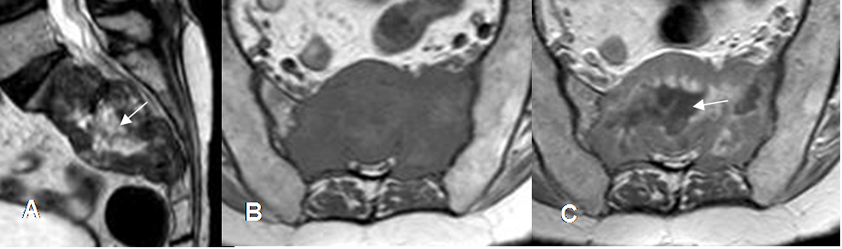

Fig 226. Metástasis líticas

A: RM sagital en T2. Lesión neoplásica que compromete el sacro, de señal heterogénea con predominio hipointenso y centro hiperintenso. (Flecha).

B: RM axial en T1 y C: RM axial en T1 con contraste. La lesión compromete el sacro y se extiende hasta el canal medular. Muestra realce heterogéneo, con centro necrótico (Flecha), secundario a lesión metastásica de neoplasia pulmonar.